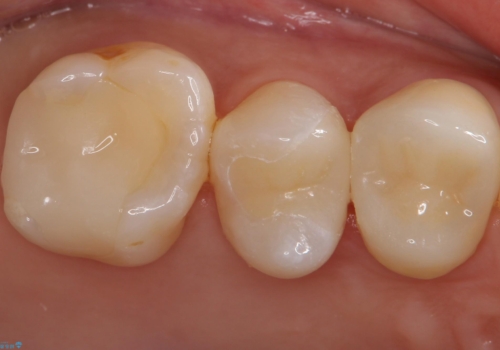

- 銀の詰め物を白くしたいとのことで来院されました。

セラミックインレーでの治療を行いました。

残る歯の厚みが確保されている場合はインレーでの修復が可能です。